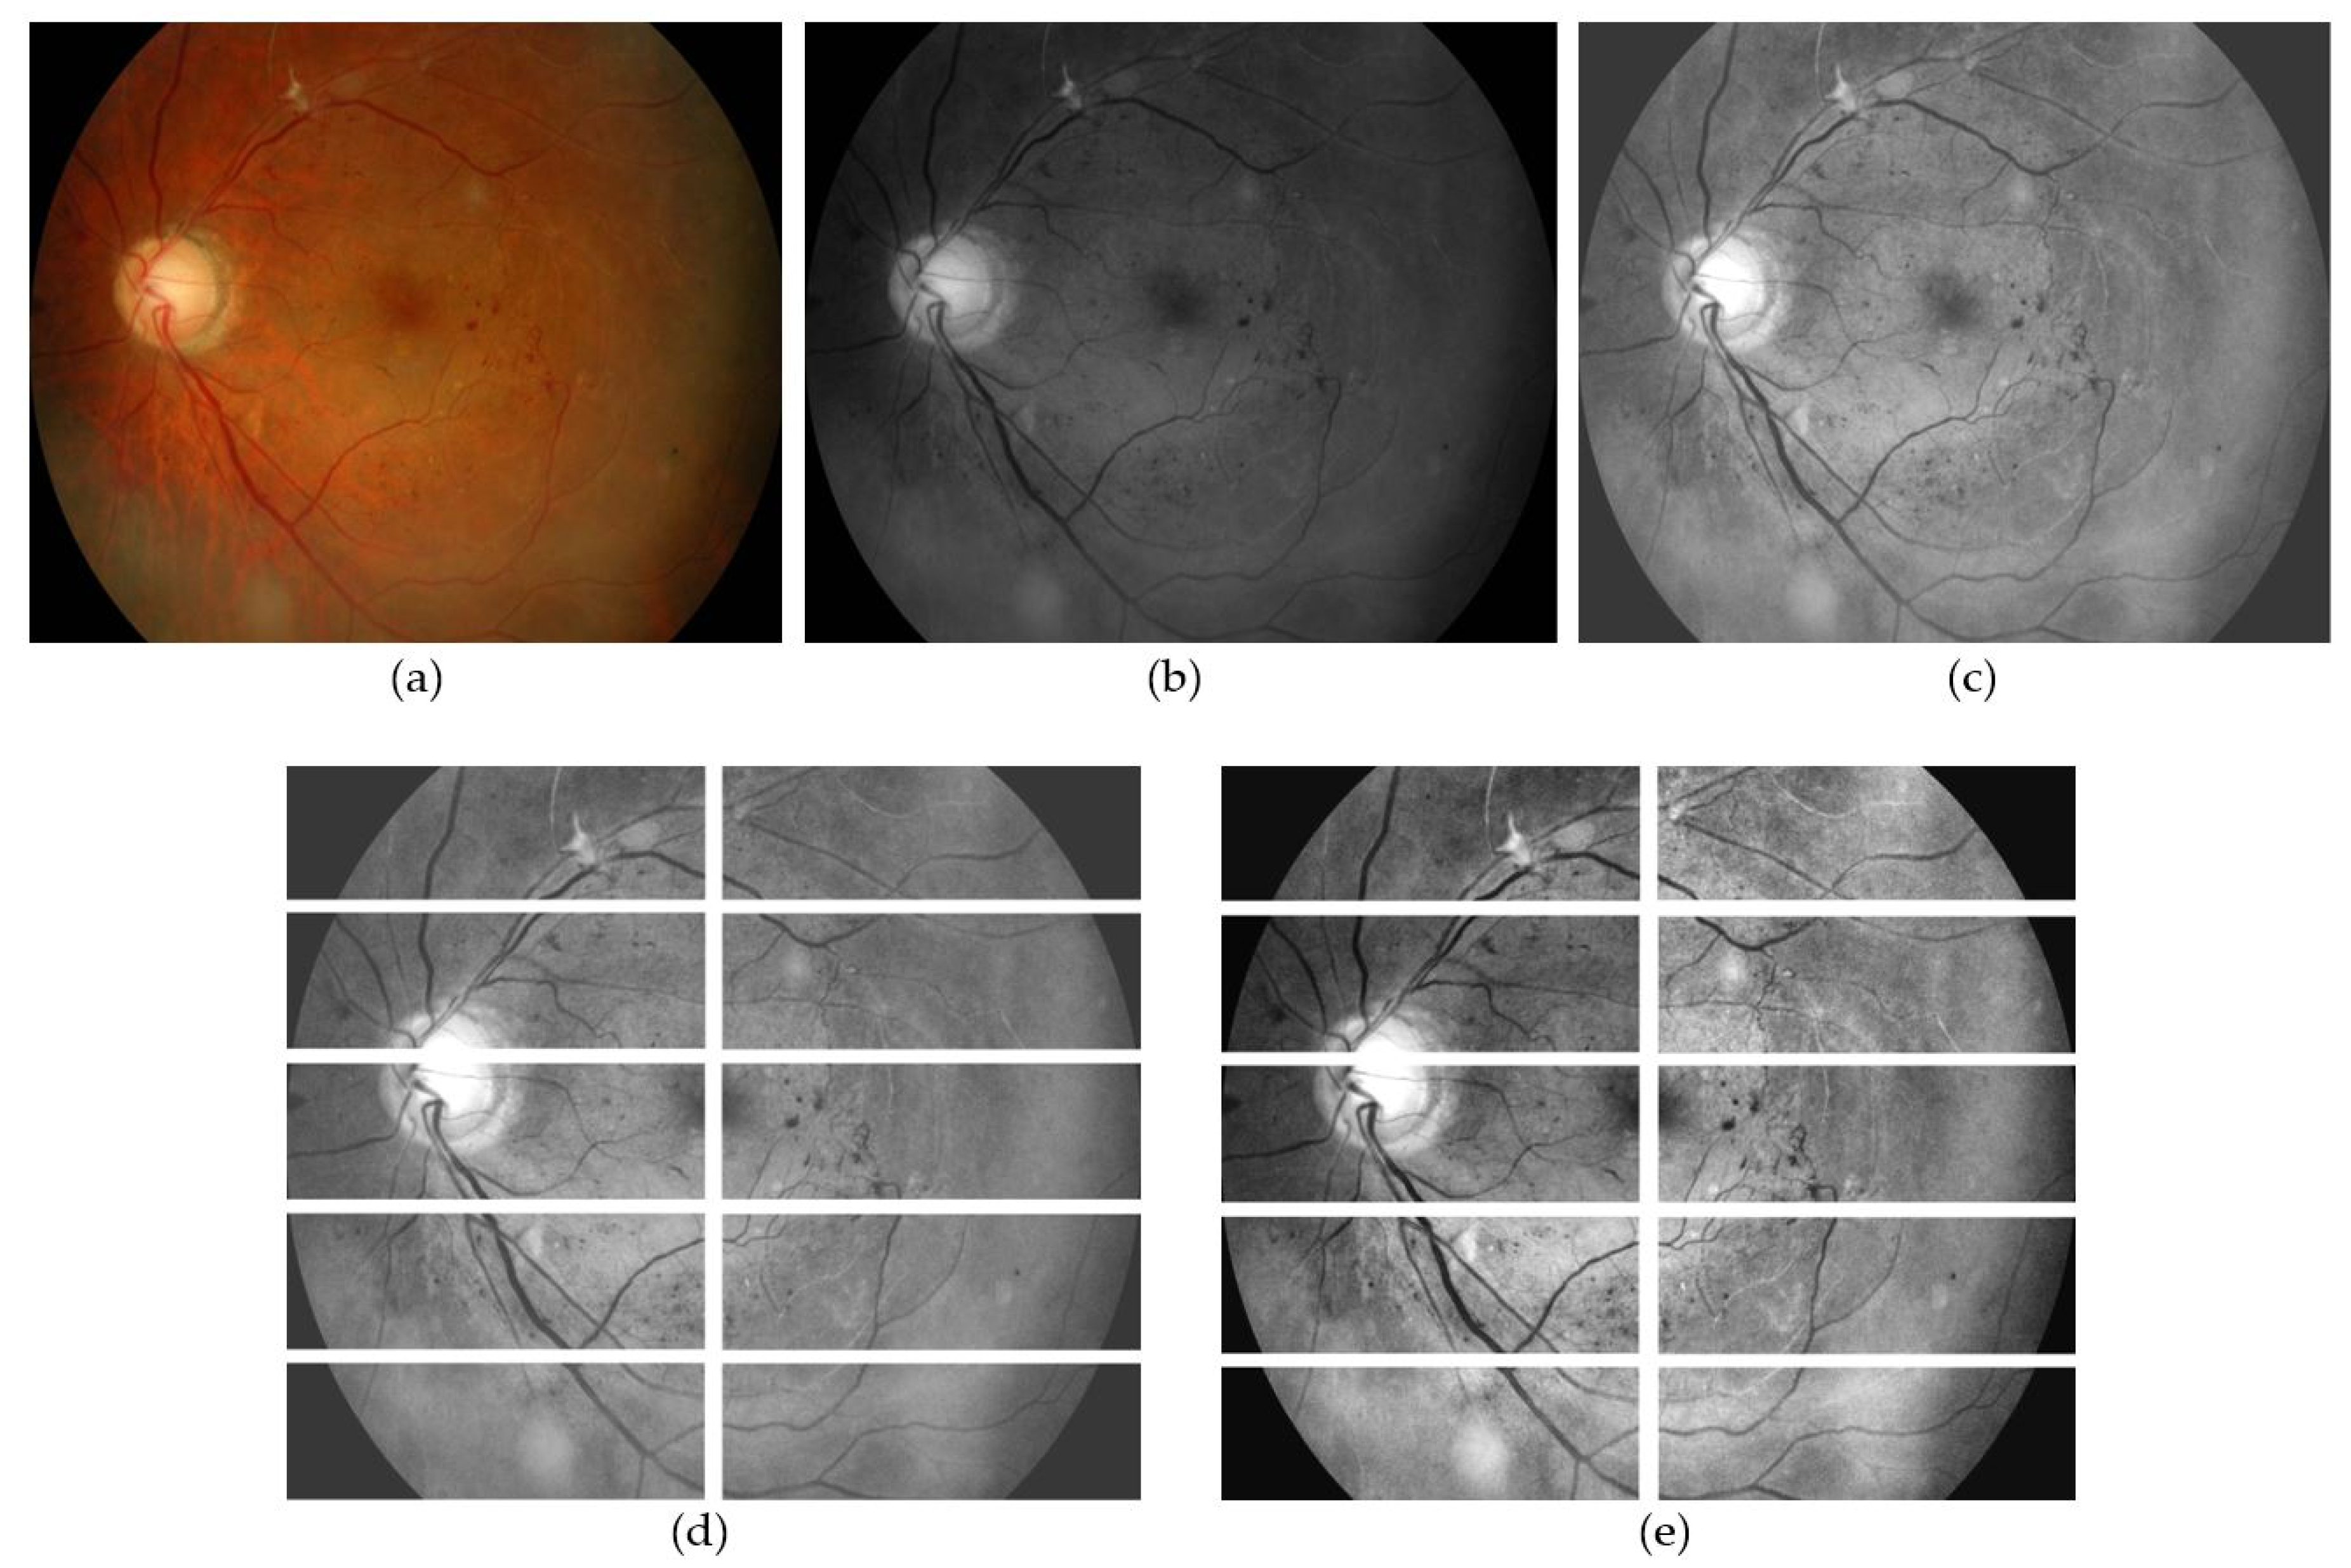

3.1. Image Pre-Processing and Data Preparation